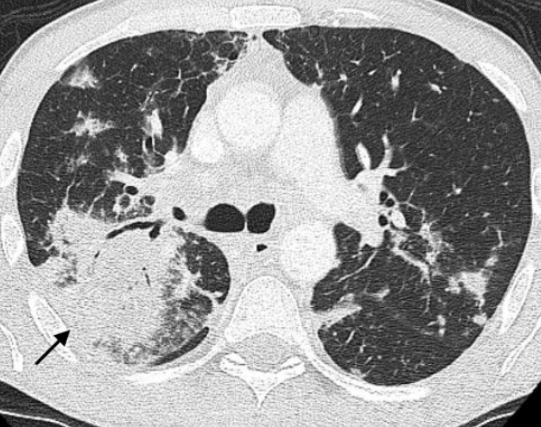

Lymphome Pulmonaire Secondaire

- Plus fréquent que le primaire

- L’atteinte dépend du type de Lymphome

- Masse / Consolidations / Epaississement péribronchovasculaire